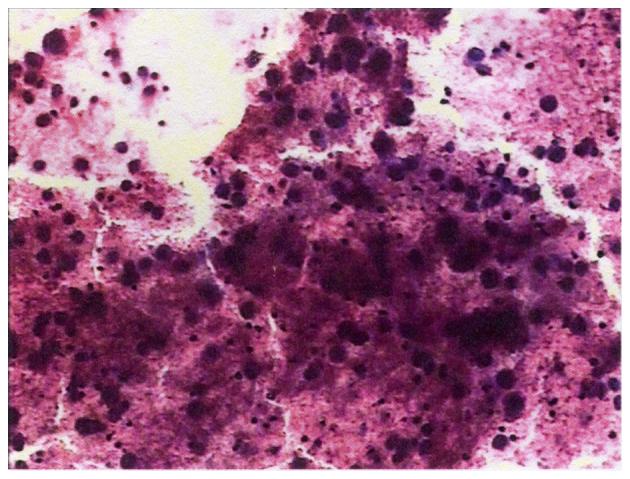

Hepatocellular carcinoma (HCC) metastases in the mediastinum are rare, particularly under the arch of the aorta. The present study describes the case of a 30-year-old male patient who presented with back pain and hoarseness for 2 months due to lymph node metastasis of HCC. The patient had undergone right hepatic lobectomy for HCC 2 years prior and received transarterial chemoembolization 4 times following resection. A computed tomography scan revealed enlarged lymph nodes under the arch of the aorta that appeared to have invaded the left recurrent laryngeal nerve, causing the hoarseness. Percutaneous aspiration biopsy of the enlarged, right supraclavicular lymph node identified malignant cells consistent with HCC. Radiation administered as a therapy to treat for the metastatic lymph nodes did not diminish the tumor but relieved the symptoms.

肝细胞癌(HCC)转移至纵隔罕见,尤其是在主动脉弓下方。本研究描述了一名30岁男性患者的病例,该患者因HCC淋巴结转移出现背痛和声音嘶哑2个月。患者2年前因HCC接受了右肝叶切除术,术后接受了4次经动脉化疗栓塞术。计算机断层扫描显示主动脉弓下方淋巴结肿大,似乎侵犯了左喉返神经,导致声音嘶哑。对肿大的右侧锁骨上淋巴结进行经皮穿刺活检,发现了与HCC一致的恶性细胞。作为转移性淋巴结治疗手段的放疗并未使肿瘤缩小,但缓解了症状。